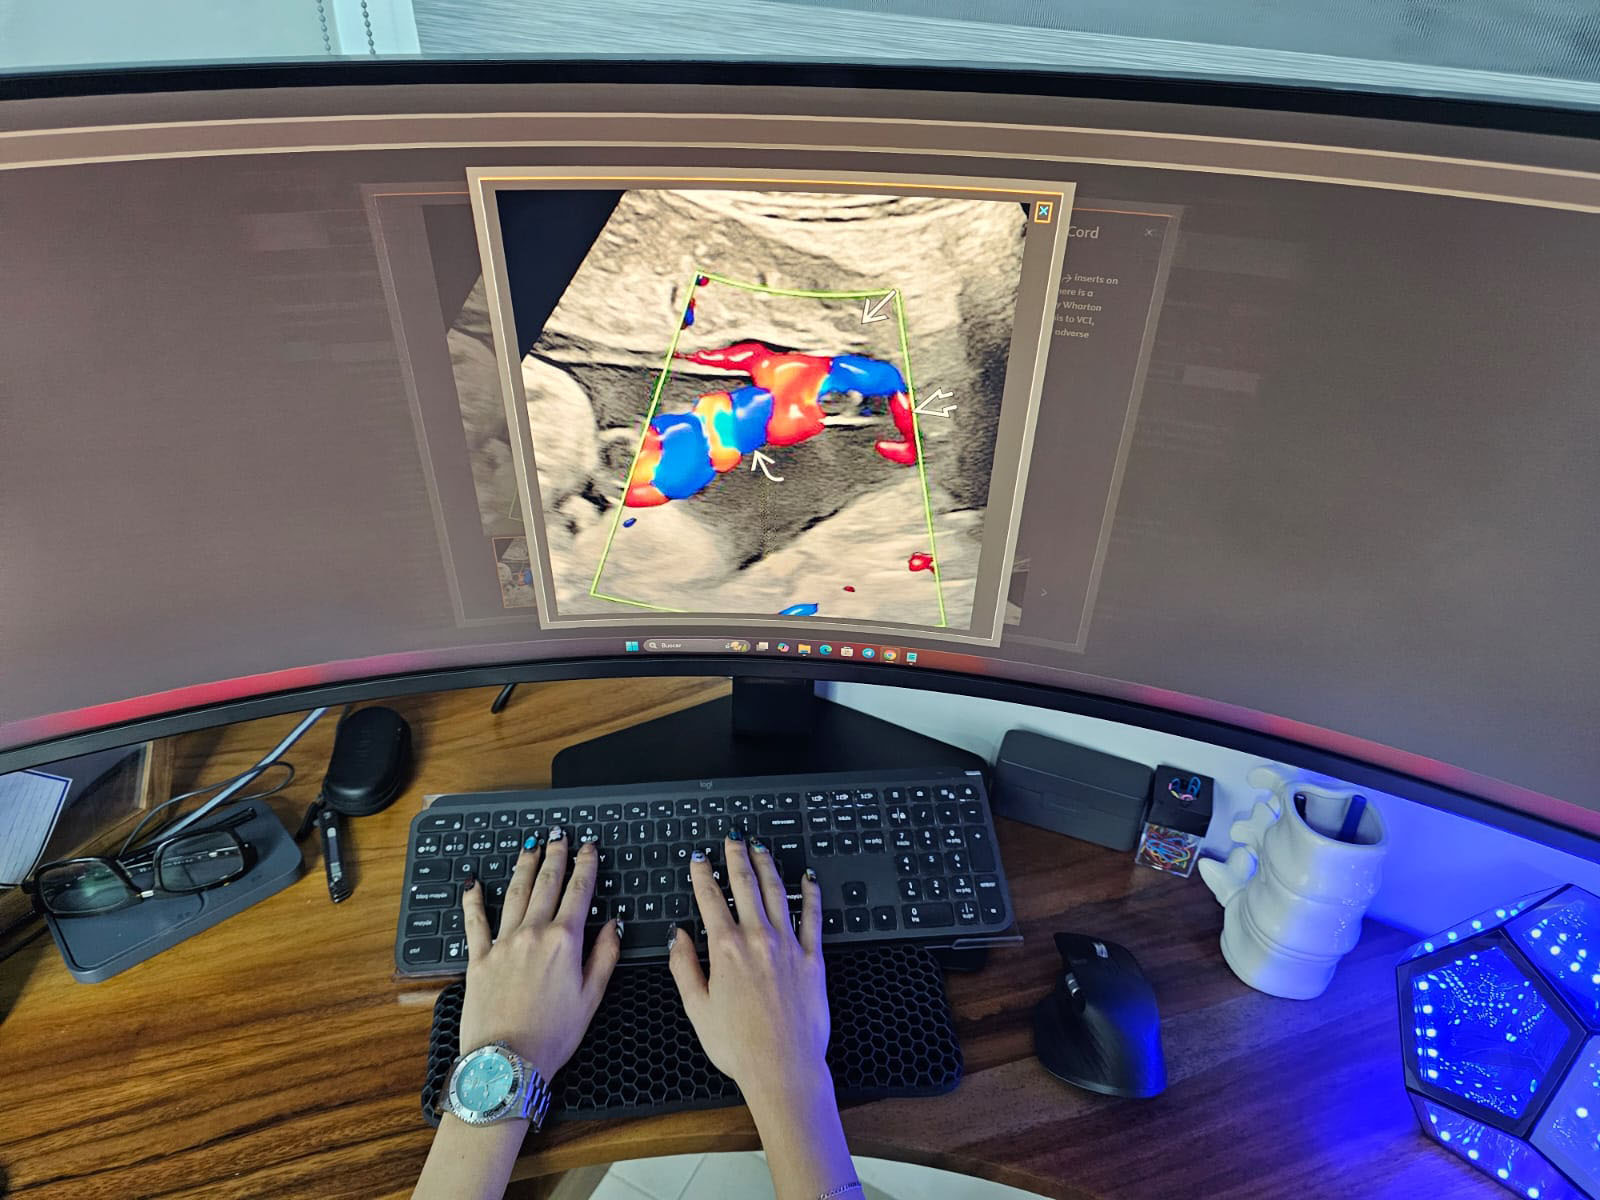

Diagnóstico por ultrasonido con precisión y calidez humana.

En Eco Scanner ofrecemos estudios de ultrasonido realizados por un médico radiólogo especialista, garantizando:

- Presición diagnóstica.

- Trato humano y cercano.

- Resultados confiables en un ambiente cómodo, seguro y profesional.